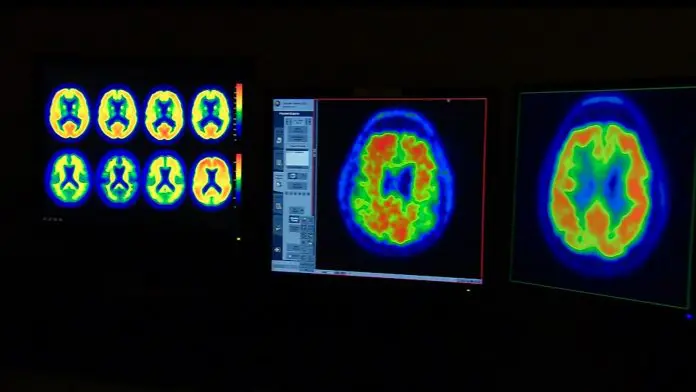

إرشادات جديدة لعلاج إصابات الدماغ.. إليك ما ينبغي معرفته

تُعدّ إصابات الدماغ الرضّية سببًا رئيسيًا للوفاة والإعاقة في الولايات المتحدة. وهي أكثر شيوعًا ممّا تتصوّر، إذ تُصيب ملايين الأمريكيين سنويًا. كانت إصابات الدماغ الشديدة تُعتبر في السابق بمثابة حكم بالإعدام، لكن لأول مرة منذ عقود، قد يُغيّر معيار جديد للرعاية الصحية هذا الواقع.